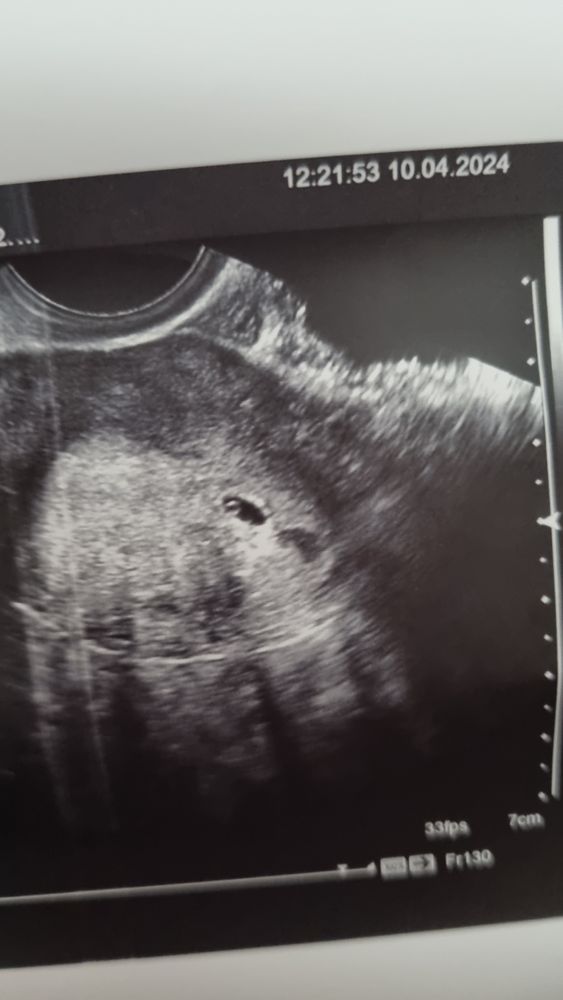

В этом цикле без тестов, но уже с первым фото нашей долгожданной крошки

Но есть фото)) так что вроде как не сон

Узистка напугала маленьким размером пя

5,4×3,5

Вроде как не соответствует сроку 4,5 н

Не переживайте, 24.04 как раз все увидите и услышите сердцебиение. Торопливость в этом деле не нужна, я в этом лично убедилась. А скрининг это только на 12 неделе делают примерно. Так что пока это просто УЗИ. Судя по фото у вас уже есть желточный мешочек, значит скоро появится эмбриончик, он всегда после мешочка появляется, у меня через неделю только появился, так что записались вы на нужное время!